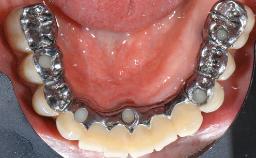

This case describes the ongoing management of a 64-year-old healthy, non-smoking female patient with erosive oral lichen planus (OLP) affecting the gingivae and the buccal and lingual mucosa. The peri-implant mucosa was also affected subsequent to implant placement. The patient had osseointegrated implants (four in the maxilla, four in the mandible) placed following extraction of hopeless teeth and a healing period. The patient had a history of OLP prior to implant placement and had been referred to an oral-medicine specialist for definitive diagnosis and treatment. She exhibited generalized oral mucosal involvement. Following a clinical assessment, biopsy, and blood tests, she was treated with topical corticosteroids. Systemic prednisolone was reserved for severe flare-ups. Amphotericin lozenges were used in combination with corticosteroid treatment to prevent the development of oral candidiasis.